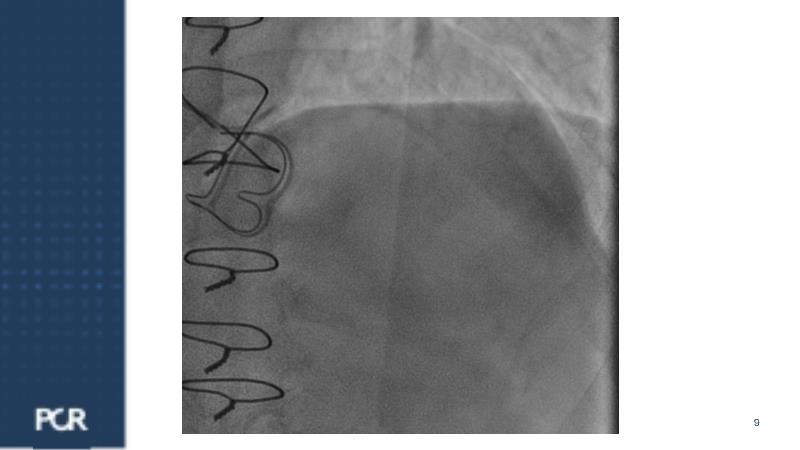

Watch this session focused on a patient with distal left main stenosis to understand that the stepwise provisional side branch (SB) stenting strategy is the standard approach for most left main trifurcation lesions. Discover the importance of optical frequency domain imaging for strategy determination and bifurcation PCI outcome optimization. Learn about the Ultimaster Nagomi™ DES, inheriting features from the Ultimaster Tansei™ stent, tailored for complex bifurcation anatomy with enhanced deliverability and overexpansion capacity.